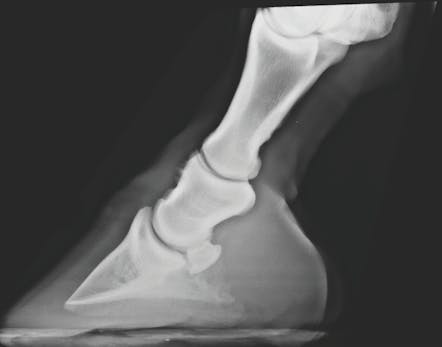

The long pastern bone is the second phalanx in a horse's digit and is situated between the short pastern bone (the proximal phalanx or P1) and the coffin bone (the third phalanx or P3). It is a relatively long and slender bone located above the hoof and below the fetlock joint.

When a horse displays signs of lameness in the lower limb, particularly in the area of the long pastern bone, a veterinarian should be consulted for a thorough examination and diagnosis. Diagnostic tools like X-rays may be used to assess the condition of the long pastern bone.